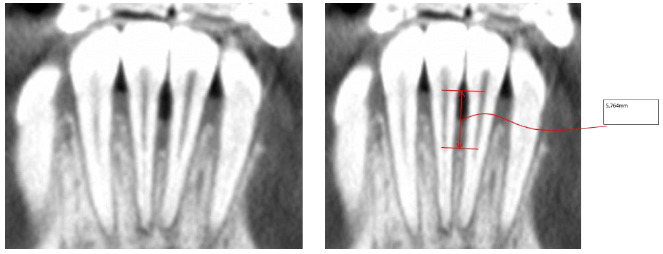

2.3. Individual Tooth Model Extraction

The individual tooth anatomies are not so simple to extract from tomographic data because of similar grey intensity values of the tooth root and surrounding bone tissue. Slice-by-slice segmentation procedures are commonly used for this purpose, but this can result in processing hundreds of slices in order to obtain segmented models, thus leading to time-consuming procedures. In this case, DICOM images were processed by adopting the methodology introduced in the paper by Barone et al. [10]. This method is based on processing a subset of images (reformation images) for each tooth on the basis of anatomy-driven considerations. The reformation images allowed us to easily obtain the tooth geometry by using a limited set of 2D curves representing the contour of the tooth in each image. Indeed, four reference planar sections were automatically obtained. These reference sections were used to outline the tooth by tracing four different 2D curves that represented the tooth contours (Fig. 4a). The four contours were used to automatically extract a series of closed curves on each slice perpendicular to the tooth axis (transverse slice) (Fig. 4b).

This methodology allowed us to rapidly extract the geometry of a full tooth by means of manually processing a few automatically extracted images from CBCT data. The processing time was significantly lowered compared to common manual standard methods.